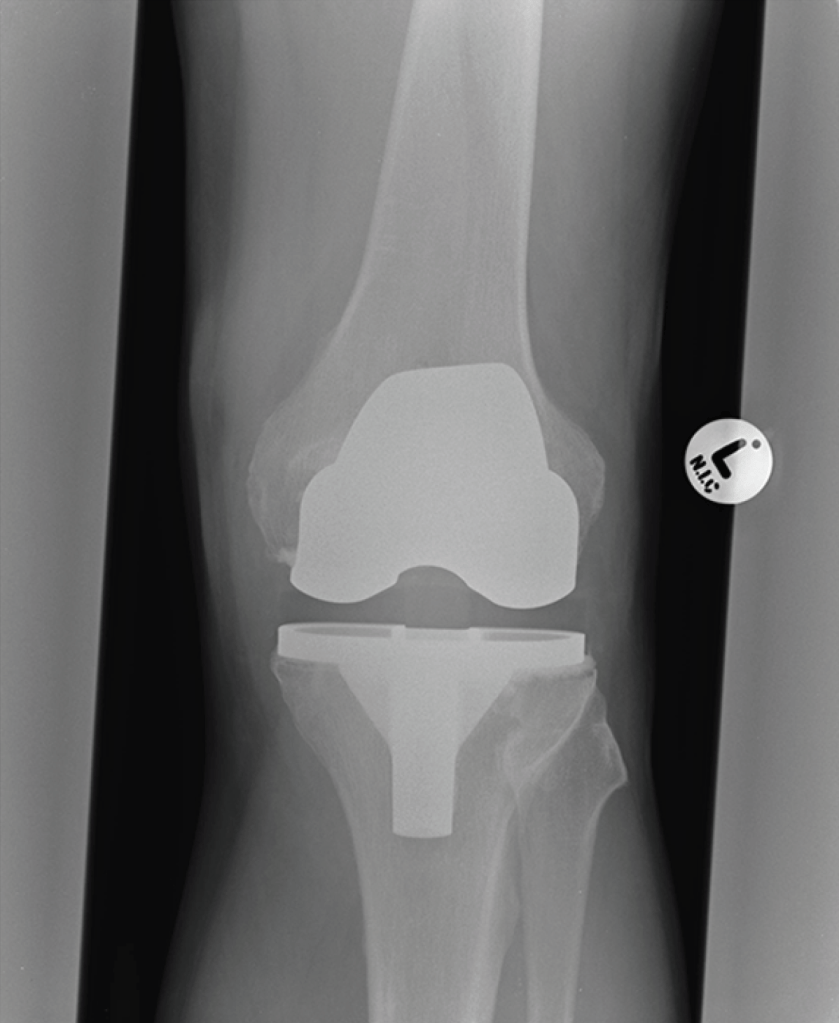

This is a case report of an infection in a prosthetic knee joint following acupuncture. A 65-year-old man who had undergone TKR for osteoarthritis 2 years previously received acupuncture treatment for hay fever that included insertion of a needle on the medial aspect of his knee. Three days later he attended the emergency department with a swollen painful knee. I am assuming it was the left knee from the x ray film with a big ‘L’ on it, but the report is a little slim on that sort of detail. Instead we have lots of details of blood tests, antibiotics and, of course, the rather rare bug responsible for the infection – Granulicatella adiacens.

Judging by the soft tissue shadow on the x ray film the prosthesis was between about 10 to 20mm beneath the surface on both medial and lateral aspects of the knee, so inoculation with an acupuncture needle is certainly possible. Spontaneous infection via a haematogenous route is also possible, but this would be a rather less likely coincidence at day 3 following needle insertion at the same site.